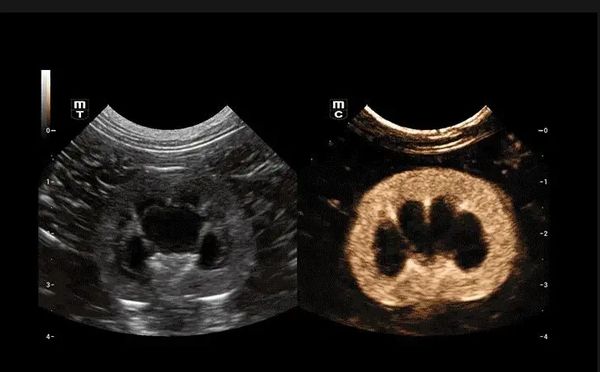

Similar al espíritu inherentemente rápido y nítido de un jaguar, Vetus 9 ofrece imágenes 10 veces más rápidas, enfoque dinámico de píxeles y tecnologías originales de recuperación de señal ecográfica, lo que permite a los veterinarios enfrentarse a todos los escenarios clínicos con facilidad.

La plataforma ZST+ es una innovación extraordinaria, que representa una evolución de la tecnología de ultrasonidos. Transforma las métricas de los ultrasonidos de la formación de haces convencional al procesamiento basado en canales. Supera la tradicional limitación de compensación entre resolución espacial, resolución temporal y uniformidad tisular, proporcionando una calidad de imagen excepcional en diversos escenarios clínicos veterinarios y ofreciendo una confianza notable.